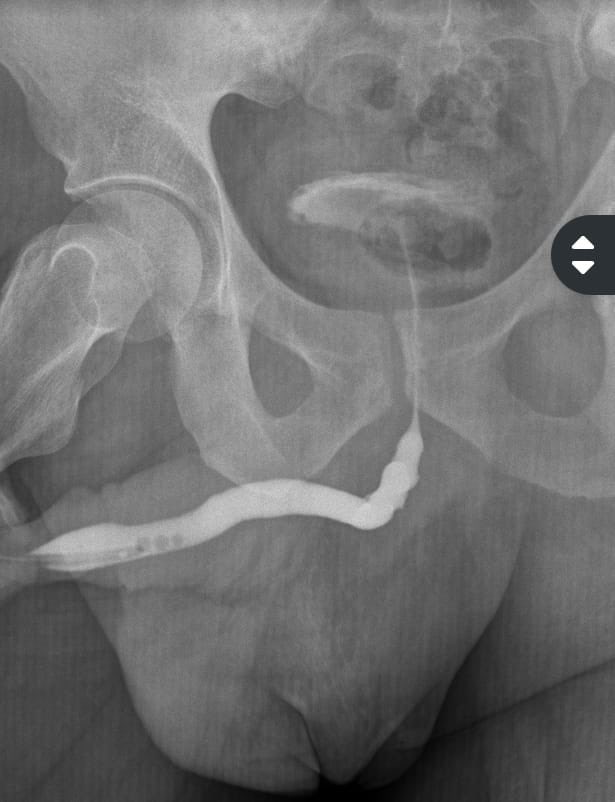

36 años estrechez uretral, una semana previa a la cirugía hizo RAO, se colocó talla y se realizó Plastia de uretra con BMG. Uretrograma de control con buenos resultados.